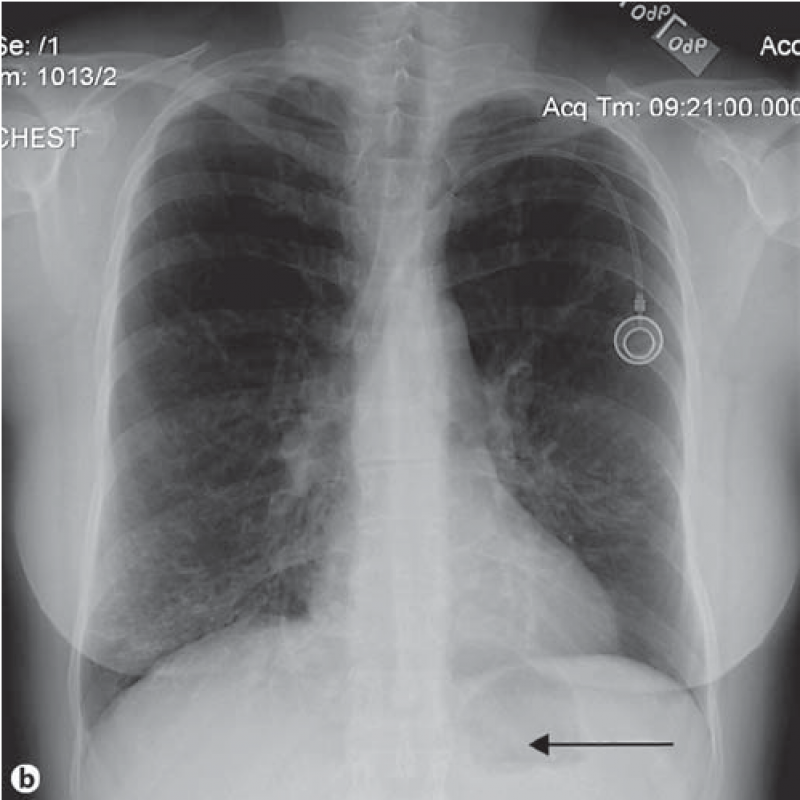

Exame de Imagem de Tomografia do Tórax

Exame de Imagem de Tomografia do Tórax

Exame de Imagem de Tomografia do Tórax

Medicom ExamesUm exame de imagem é uma fase do processo de diagnósticos e tratamentos. Um exame de imagem é uma forma de permitir que os médicos possam ver e... Cotar Agora Saiba Mais